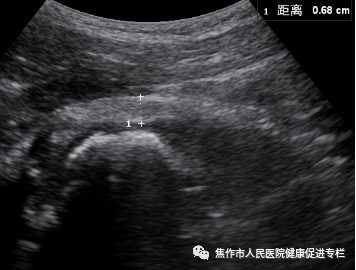

髋关节囊正常声像图

(1)小儿髋关节前隐窝正常情况下可有积液,起润滑作用,但是一般<2mm。

(2)关节囊厚度<6mm。